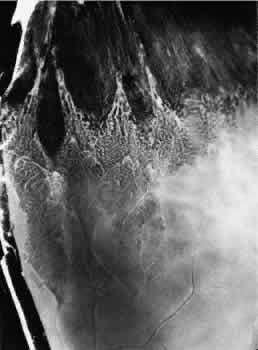

Retinoschisis associated with a bullous architecture and prominent reticular cystoid degeneration has been termed reticular degenerative retinoschisis. Reticular degenerative retinoschisis can be distinguished from typical degenerative retinoschisis by the large extent of retinal involvement, a round or ovoid configuration with bullous elevation of the extremely thin inner layer, and an irregular, pitted outer layer (Figs. 20 and 21). Typical cystoid degeneration is always present anterior to the schisis; reticular cystoid degeneration is usually prominent at some site in the involved eye. Blood vessels coursing through the inner layer give it an arborizing reticular pattern on contact lens biomicroscopy. The intraretinal cavity is optically empty; the outer wall is irregularly excavated to produce a pocked or honeycomb appearance. Round or ovoid holes are often present in the outer retinal layer; they are single or multiple, frequently large, and usually associated with a rolled posterior edge.13

Fig. 20. Reticular degenerative retinoschisis. Note reticulated, highly elevated, inner wall with a conspicuous delicate vascular pattern. Radial columns of the retina are completely disrupted within the region of bullous elevation, and the retinoschisis extends posterior to the equator. (× 18.)

Microscopic sections demonstrate the extremely attenuated, blood vessel-containing inner layer composed of the internal limiting membrane and remnants of the nerve fiber layer (Fig. 22). The honeycomb appearance of the outer layer corresponds to irregular excavations. In some areas, the outer layer is made up of outer plexiform, outer nuclear, external limiting, and rod and cone layers; in other areas it is reduced to only the external limiting and the rod and cone layers; round or ovoid holes may be present (Fig. 23).

Reticular degenerative retinoschisis is evident in 1.6% of adult patients, is bilateral in only 16% of these, and thus is noted in 0.95% of adult eyes (see Table 3). The lesion is found most commonly in the inferior temporal quadrant. A band of typical cystoid degeneration always separates the schisis from the ora serrata; the schists usually reaches the equator and often extends appreciably into the posterior retina.

On contact lens biomicroscopy, many retinal blood vessels present irregular contours, telangiectases, occluded segments, and microaneurysms. Between these vessels, the inner wall has a finely textured appearance and variable white, glistening particles on the vitreous side. The outer retinal wall is best seen when scleral depression produces a “white with pressure” phenomenon and reveals the honeycomb appearance. The retinal pigment epithelium often has a granular, salt-and-pepper appearance, and outer-layer retinal breaks are common. These breaks are particularly likely near the anterior and posterior margins of the schisis.